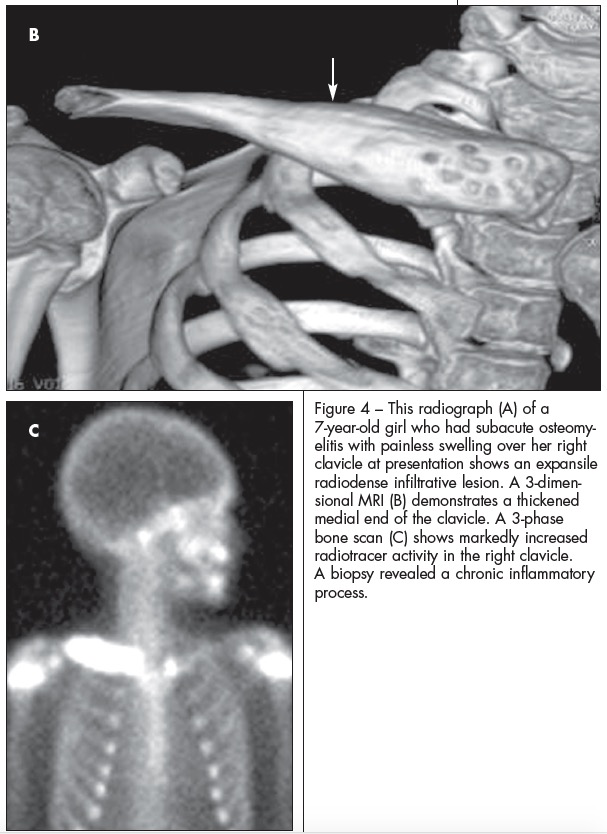

ABSTRACT: Most musculoskeletal infections in children result from hematogenous inoculation. Infections vary greatly in severity and complexity. Sequential determination of the C-reactive protein level may be the most important laboratory test in determining response to treatment. High-quality plain radiographs are essential. Ultrasonography, technetium 99m-diphosphonate scanning, and MRI also are used. In acute osteomyelitis, focal bone pain usually is accompanied by fever or malaise; antibiotic therapy is indicated. Gradual and insidious extremity pain develops in children who have subacute osteomyelitis. Classic features of chronic osteomyelitis include dead bone and reactive new bone; surgery may be needed. Typically, septic arthritis has an acute onset. Treatment includes arthrotomy and joint irrigation.